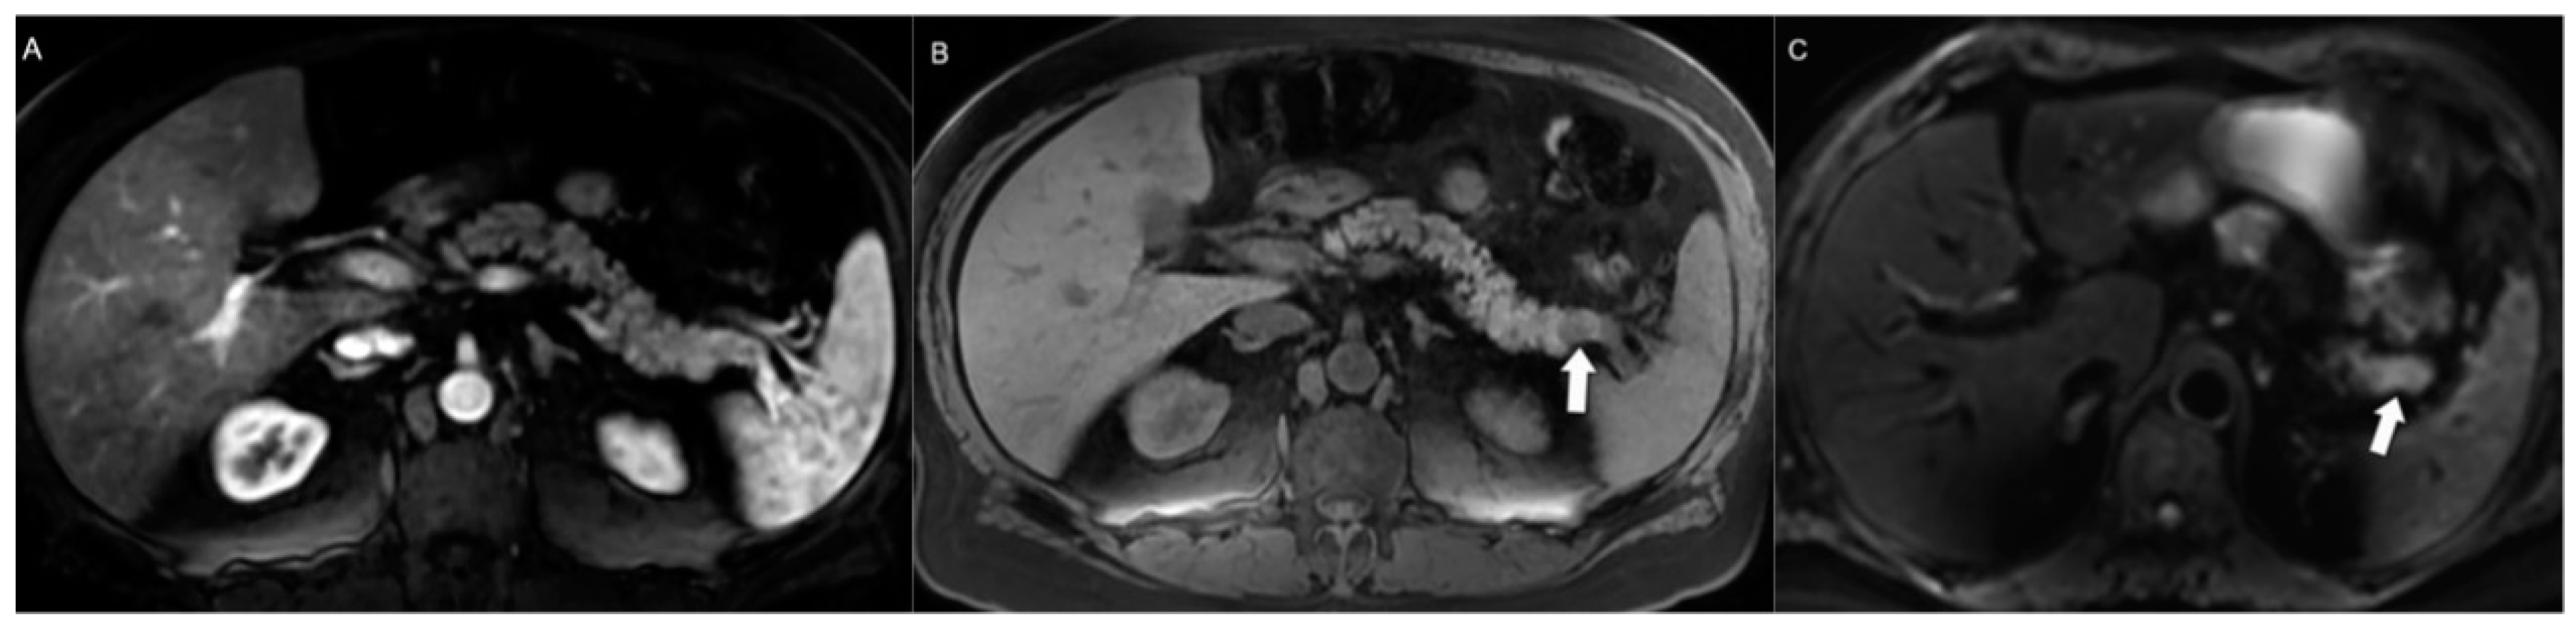

4.1. Morphologic Imaging of NENs